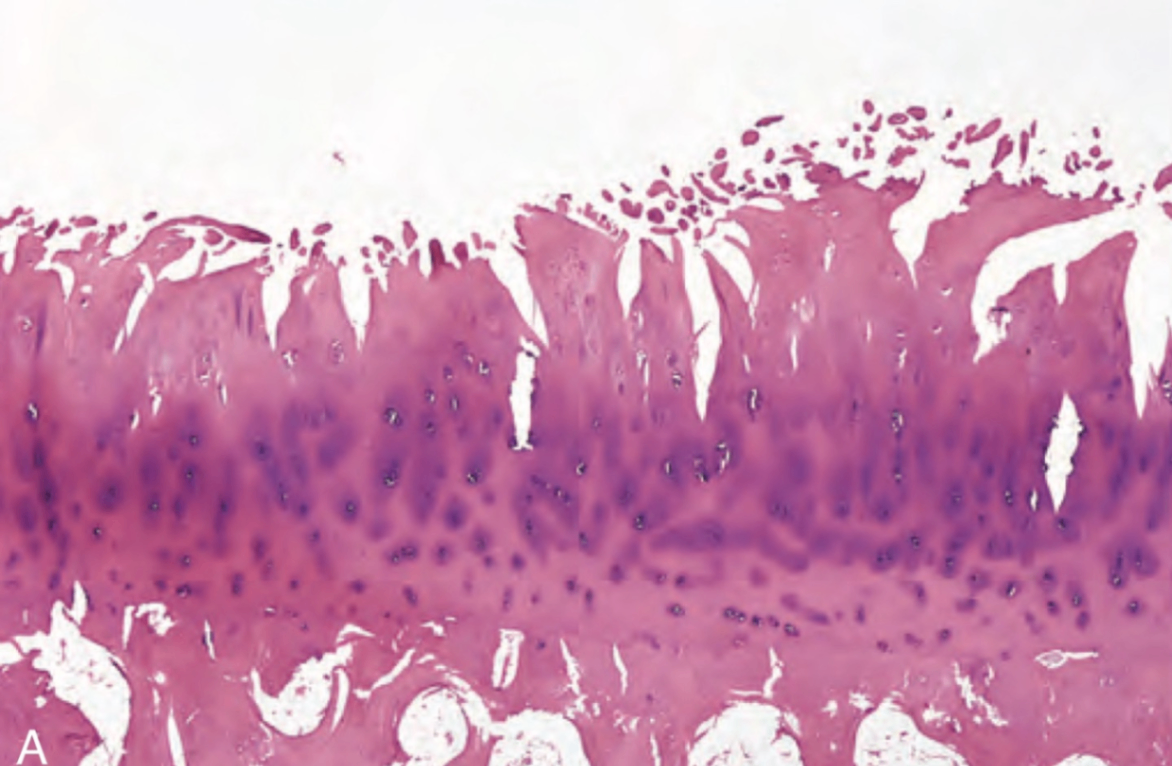

(3) 조직학적 소견

• 초기 골관절염에서는 연골세포의 증식 및 군집 형성이 관찰됨

• 이와 동시에 기질의 수분 함량 증가, proteoglycan 농도 감소, 그리고 표층부의 수평 배열된 type II collagen 섬유의 절단이 나타남

• 이러한 변화는 연골 표면에 fissure과 cleft을 유발하고 거칠고 연한 연골 표면을 노출시킴

• 또한, 연골세포가 사멸하고 전층 두께의 연골이 탈락되어 관절 내로 이탈하며 loose bodies가 관찰됨

Robbins and Cotran Pathologic Basis of Disease, 10e, pg 1199

• 노출된 subchondral bone은 관절면의 지속적인 마찰로 인해 bone eburnation이 관찰됨

• 또한, sclerosis로 인해 생긴 작은 골절들의 틈 사이로 활액이 침투 → fibrous-walled cyst 형성

• 관절면 가장자리에 fibrocartilage와 hyaline cartilage로 덮인 osteophyte가 관찰됨

활막은 대체로 경미한 충혈 및 섬유화를 보이며, 염증세포 침윤은 적음

1: eburnated articular surface exposing subchondral bone

2: subchondral cyst; 3: residual articular cartilage